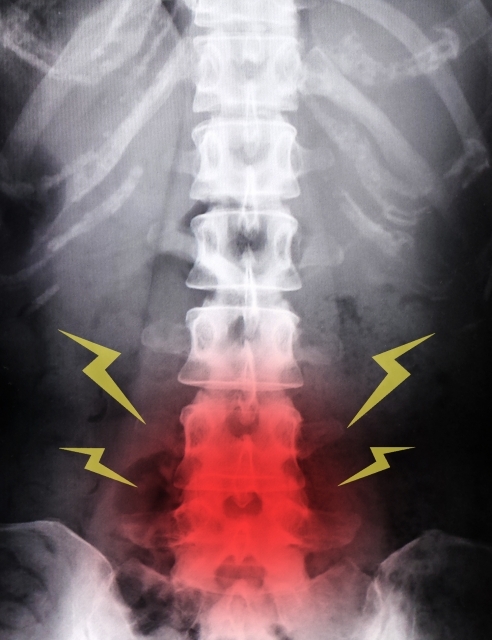

第3章:姿勢や腰痛との関係

骨の密度が低下してくると、体を支える背骨(脊椎)のバランスにも影響が出やすくなります。

• 猫背になりやすく、内臓が圧迫される

• 腰や背中の筋肉に過度な負担がかかる

• 結果として、慢性的な腰痛や全身の疲れやすさにつながる

「ただの腰痛だと思っていたら、骨の変化が背景にあった」というケースも、整形外科の現場では珍しくありません。体の不調は複数の要因が重なっていることが多いのです。